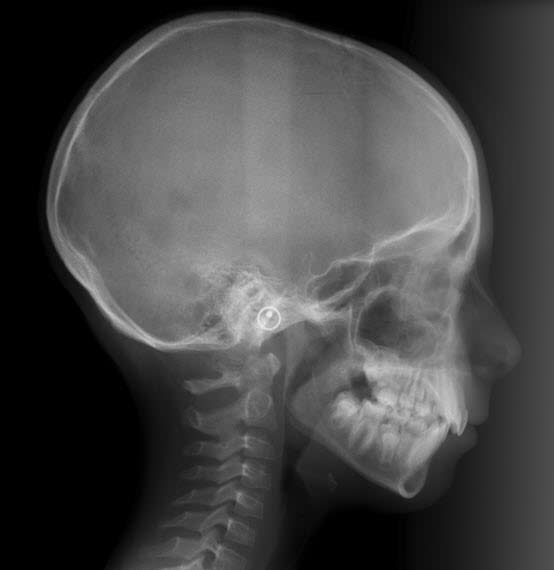

Et voici le cas de cette jeune fille deux ans plus tard, elle a alors 9 ans. On va encore attendre.